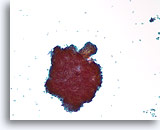

Fibroadenoom, Borst FNA, celblok.

Kenmerkende fibromyxoïde stroma is aanwezig met benigne ductale cellen.

10X

Fibroadenoom, Borst FNA, celblok.

Kenmerkende fibromyxoïde stroma is aanwezig met benigne ductale cellen.

10X

Fibroadenoom, Borst FNA, celblok.

Let op het gladde oppervlak van dit naakte fibromxyoïde stromale fragment en de eentonige morfologie van de mesenchymale kernen.

40X

Fibroadenoom, Borst FNA, celblok.

Let op het gladde oppervlak van dit naakte fibromxyoïde stromale fragment en de eentonige morfologie van de mesenchymale kernen.

40X